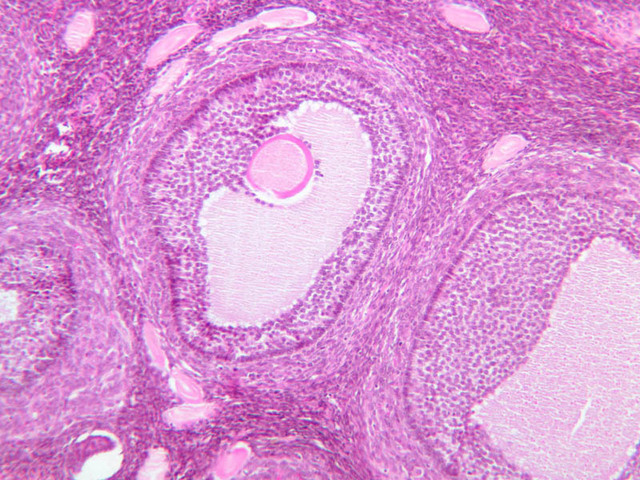

The ovary is a somewhat oval and slightly flattened organ situated near the fimbriated end of the uterine tube (B-94, monkey ovary, H&E [1x, 1x]; B-95, monkey ovary, H&E [1x-labeled, 1x]; B-96, monkey ovary and tube, H&E [1x]; B-54, H&E [1x, 1x]). Its exposed surface is covered by a mesothelial sheet of squamous or cuboidal epithelium. Just deep to this is an ill defined area of dense fibrous connective tissue referred to as the tunica albuginea (B-96 [2.5x-labeled, 10x-labeled, 20x, 40x]).

The ovary has two major regions – the cortex and the medulla. The cortex is the broad peripheral area containing follicles in various stages of development, whereas the medulla is the more central area displaying profiles of large blood vessels. These blood vessels gain entrance via the mesovarium. The division between the cortex and medulla is indistinct. In the cortex, stromal cells occupy the areas between the follicles. These cells are closely packed, fusiform (spindle shaped), and have the potential to differentiate into a specialized component of the maturing follicle (theca folliculi).

With each cycle several follicles begin the process of follicular growth and maturation. The initial morphological event in this process is the transformation of primordial follicles to primary follicles. Normally only one follicle achieves the mature state and ovulates per cycle. The remainder cease growing and degenerate at various points in the maturation process. After ovulation, at mid-cycle, the ruptured follicle persists for a short while as the functionally important corpus luteum.